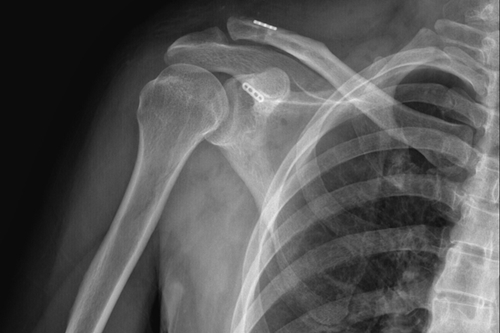

术后DR

一名50岁的男性患者,因不慎摔伤致右肩关节肿痛,并伴活动受限4天后来附院求治。入院查体发现患者右肩部肿胀明显,右锁骨远端隆起畸形,局部明显按压出现疼痛,肩部外展活动受限,进行X线检查显示“右肩锁关节脱位”。骨三科医师团队根据患者病情,进行充分商讨,确定了手术治疗方案,决定为患者实施“右肩锁关脱位复位带袢钢板内固定术”。由副主任医师蒋宇平主刀,骨三科手术团队在患者锁骨上方及喙突处各取2cm手术切口,将肩锁关节复位后,使用瞄准器由喙突基底部向锁骨远端建立骨性隧道,最后将带袢钢板由骨道穿出后固定,术中出血仅10ml左右。

骨三科主任朱述浪表示,近年来,随着生活水平的提高,患者对手术方式、手术效果的心理预期也不断提高。传统手术通过使用锁骨钩钢板来治疗肩锁关节脱位,其固定方式虽牢靠,但手术切口较大,术后极易出现脱钩、肩峰撞击,下骨溶解甚至造成骨折,疼痛发生率非常高,同时,内固定需2次手术拆除,且拆除后存在再脱位的可能。相比之下,带袢钢板内固定术能够有效恢复肩锁关节各方向的稳定性,不但符合肩锁关节生物学特性,还能最大程度地减少患者的创伤,并尽可能达到美容效果。该手术的开展,有望为广大患者提供更安全、更人性化的医疗服务。